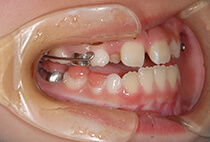

治療方法は、小さな上顎の成長誘導。

急速拡大装置と前方けん引装置を使用します。

かみ合わせもお顔立ちも大きく改善。

その後も機能訓練×かみ合わせの維持をコツコツ継続。

成長のピークに合わせて上顎をもう一度拡大し、前歯のかみ合わせをさらに安定化。

成長期の波に合わせることで、より調和の取れた横顔へ。